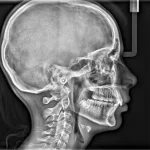

S novim Scan Ceph modulom i drugim inovacijama, najinteligentniji CBCT sustav na svijetu sada je još pametniji i svestraniji nego ikad. Sustav redefinira kvalitetu i upotrebljivost, što ga čini savršenim sustavom snimanja za stomatologe i specijaliste koji žele novu razinu preciznosti.

Kristalno jasne slike s ograničenim artefaktima i šumom